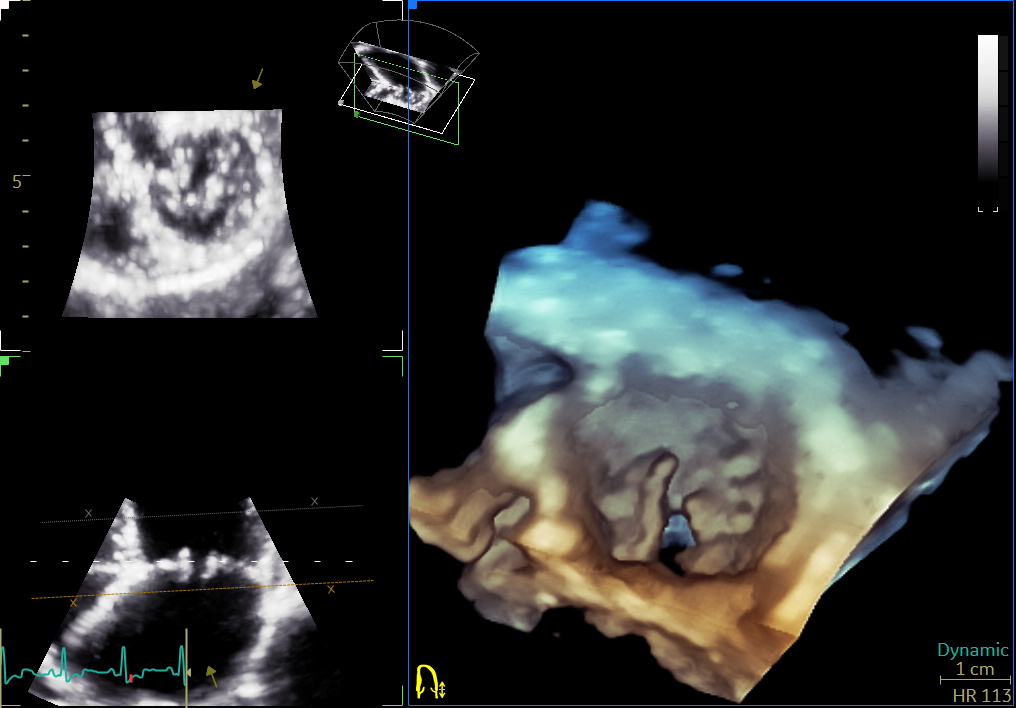

- ecocardiografia standard (modalità M-mode, 2D, Doppler, TDI, Strain e STE) e 3D;

- ecocardiografia transesofagea;

- Studio ecocardiografico 3D delle valvole cardiache nel cane